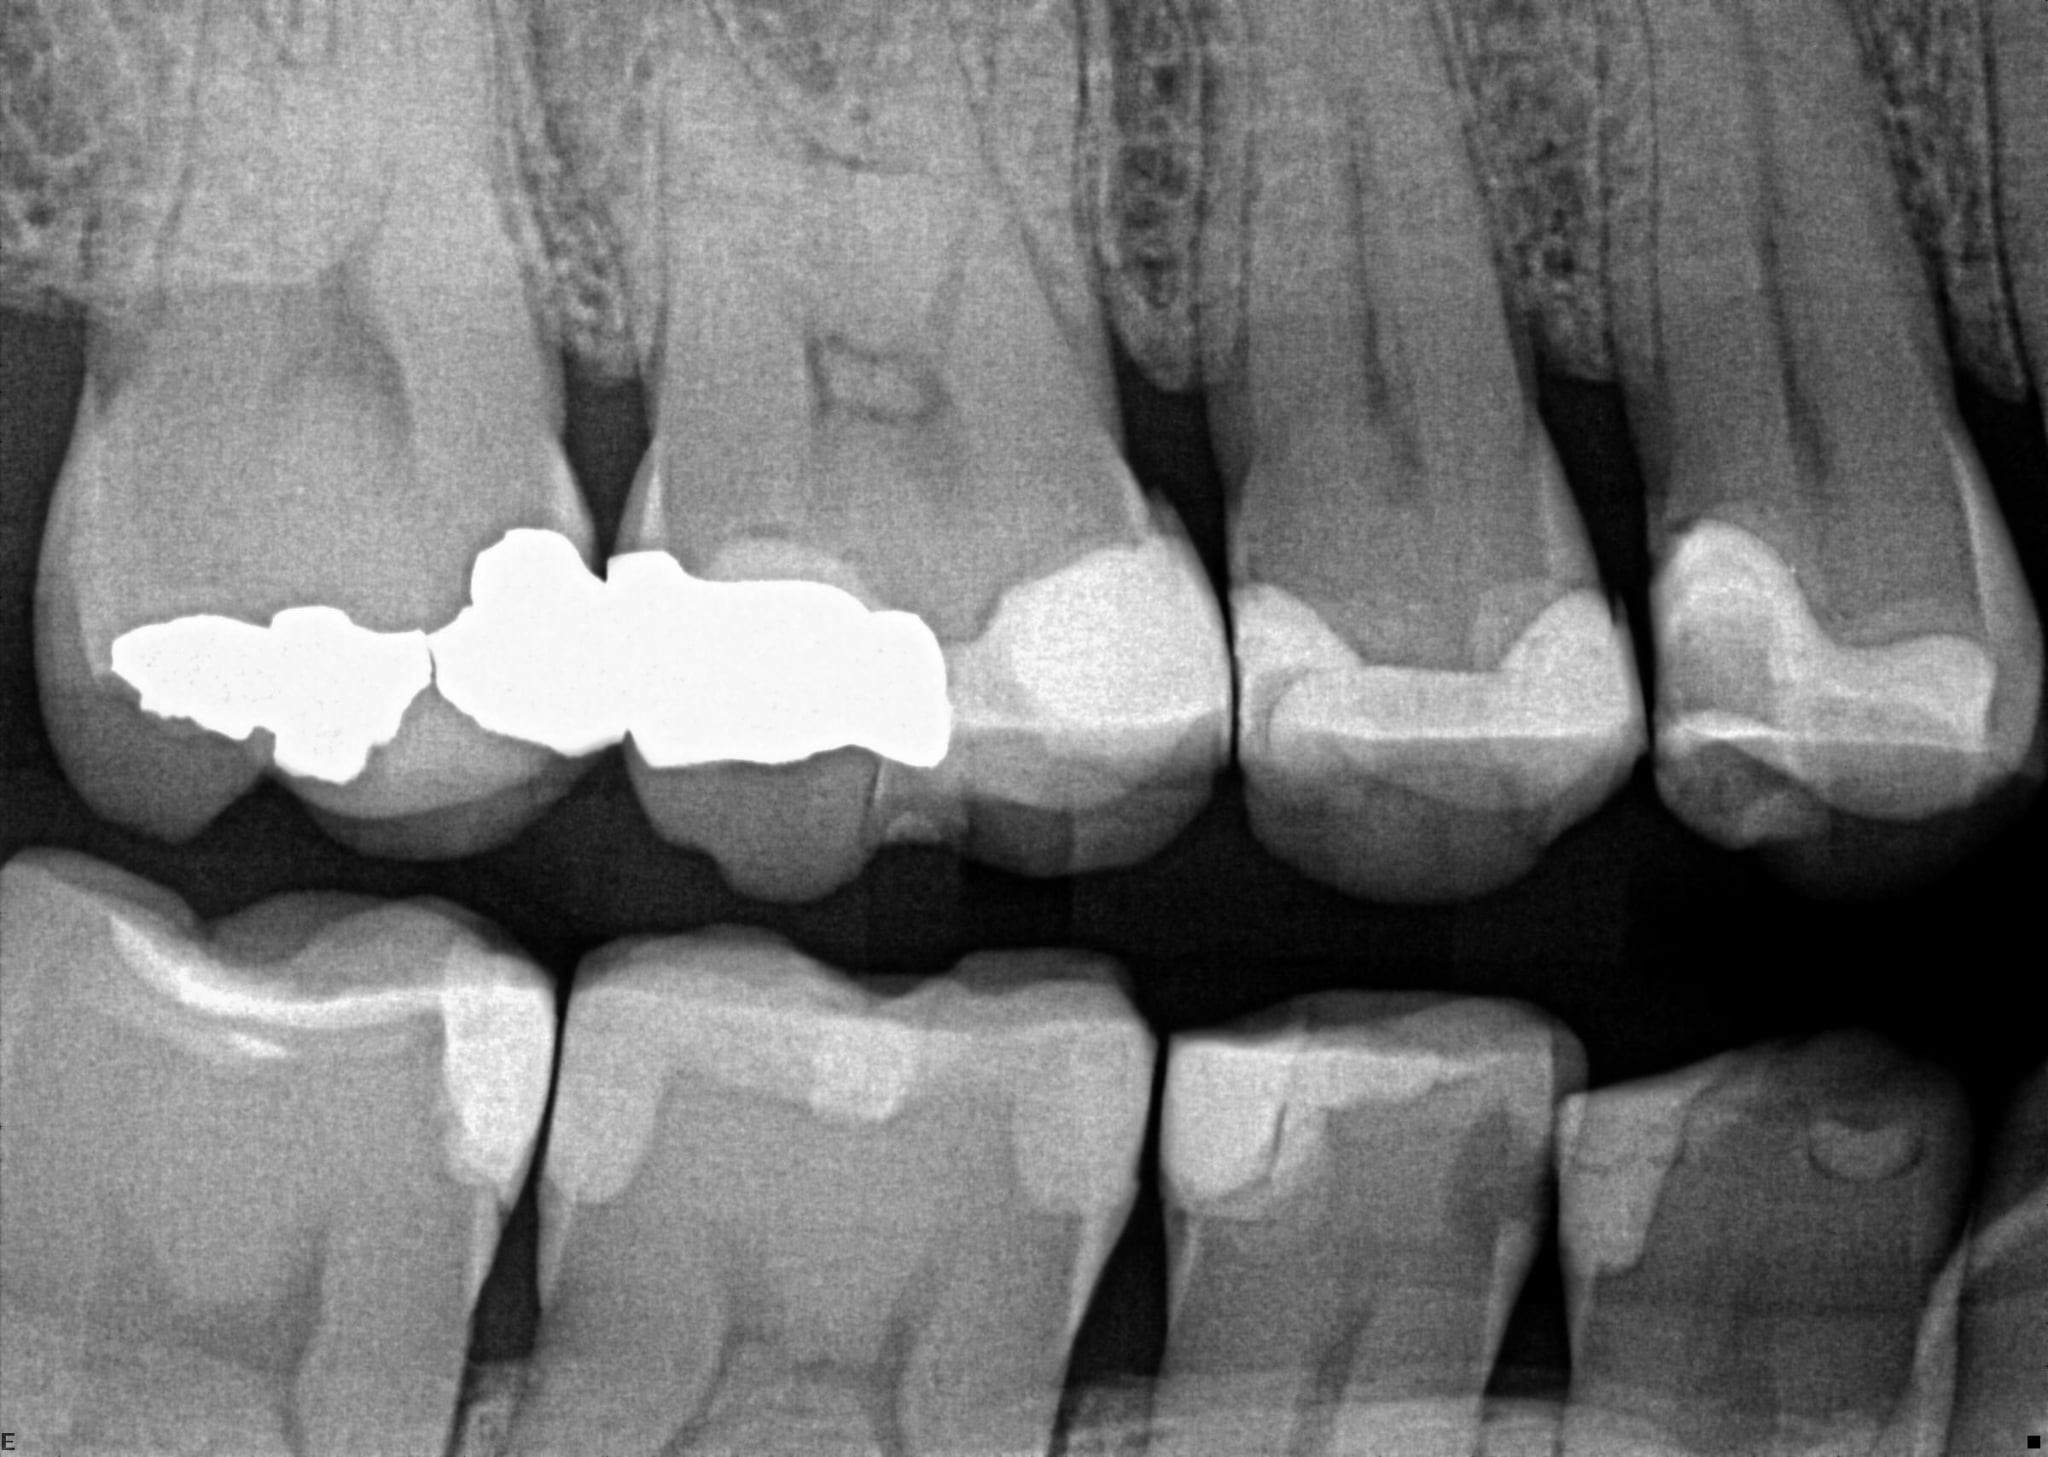

4. On which surface a recurrent caries can be detected?

distal tooth # 2.5 is bonding pooling

5 / 35

5. On which surface a recurrent caries can be detected?

the radiolucent area in mesial and distal tooth # 3.6 are bonding